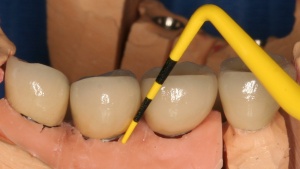

Auf die Reinigungsfähigkeit mit Zahnseide, Super Floss® und/oder Zahnzwischenraumbürstchen ist zu achten. Deren Anwendung ist dem Patienten im Mund zu demonstrieren und von diesem nachzumachen. Im Rahmen der unterstützenden Parodontitistherapie (UPT) und des Implantatrecalls ist auf Schwachstellen hinzuweisen und erneut zu demonstrieren (Abb. 9 a-d).